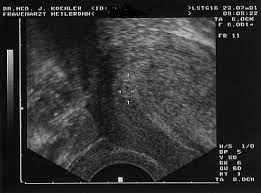

4 ssw ultraschall fruchthöhle. SSW Fruchthöhle Dottersack aber kein Embryo. Hier sieht man deutlich die schwarze Fruchthöhle der Embryo lässt sich noch nicht erkennen. Dies dient als ersten Anhaltspunkt für das Alter deiner Schwangerschaft.

Aber lässt sich auf dem Ultraschall in der 4. Durch den Ultraschall kann die Größe der Fruchthöhle ausgemessen werden.

Keine fruchthöhle sichtbar wie groß in ssw 4 4. Kann da doch noch ein Embryo drin sein letzter Ultraschall bei 7 6 2. Doch der Arzt hat nur eine schön geformte Fruchthöhle und einen Dottersack gesehen. Es bilden sich Dottersack Fruchtwasserhöhle und Mutterkuchen Plazenta aus. Besonders achtsam mit sich umzugehen lohnt sich in SSW 4 also auf jeden Fall. Da erst in der 4. Nur Fruchthöhle zu sehen bei 70 SSW. Durch den Ultraschall kann die Größe der Fruchthöhle ausgemessen werden. Der Durchmesser der Fruchthöhle.